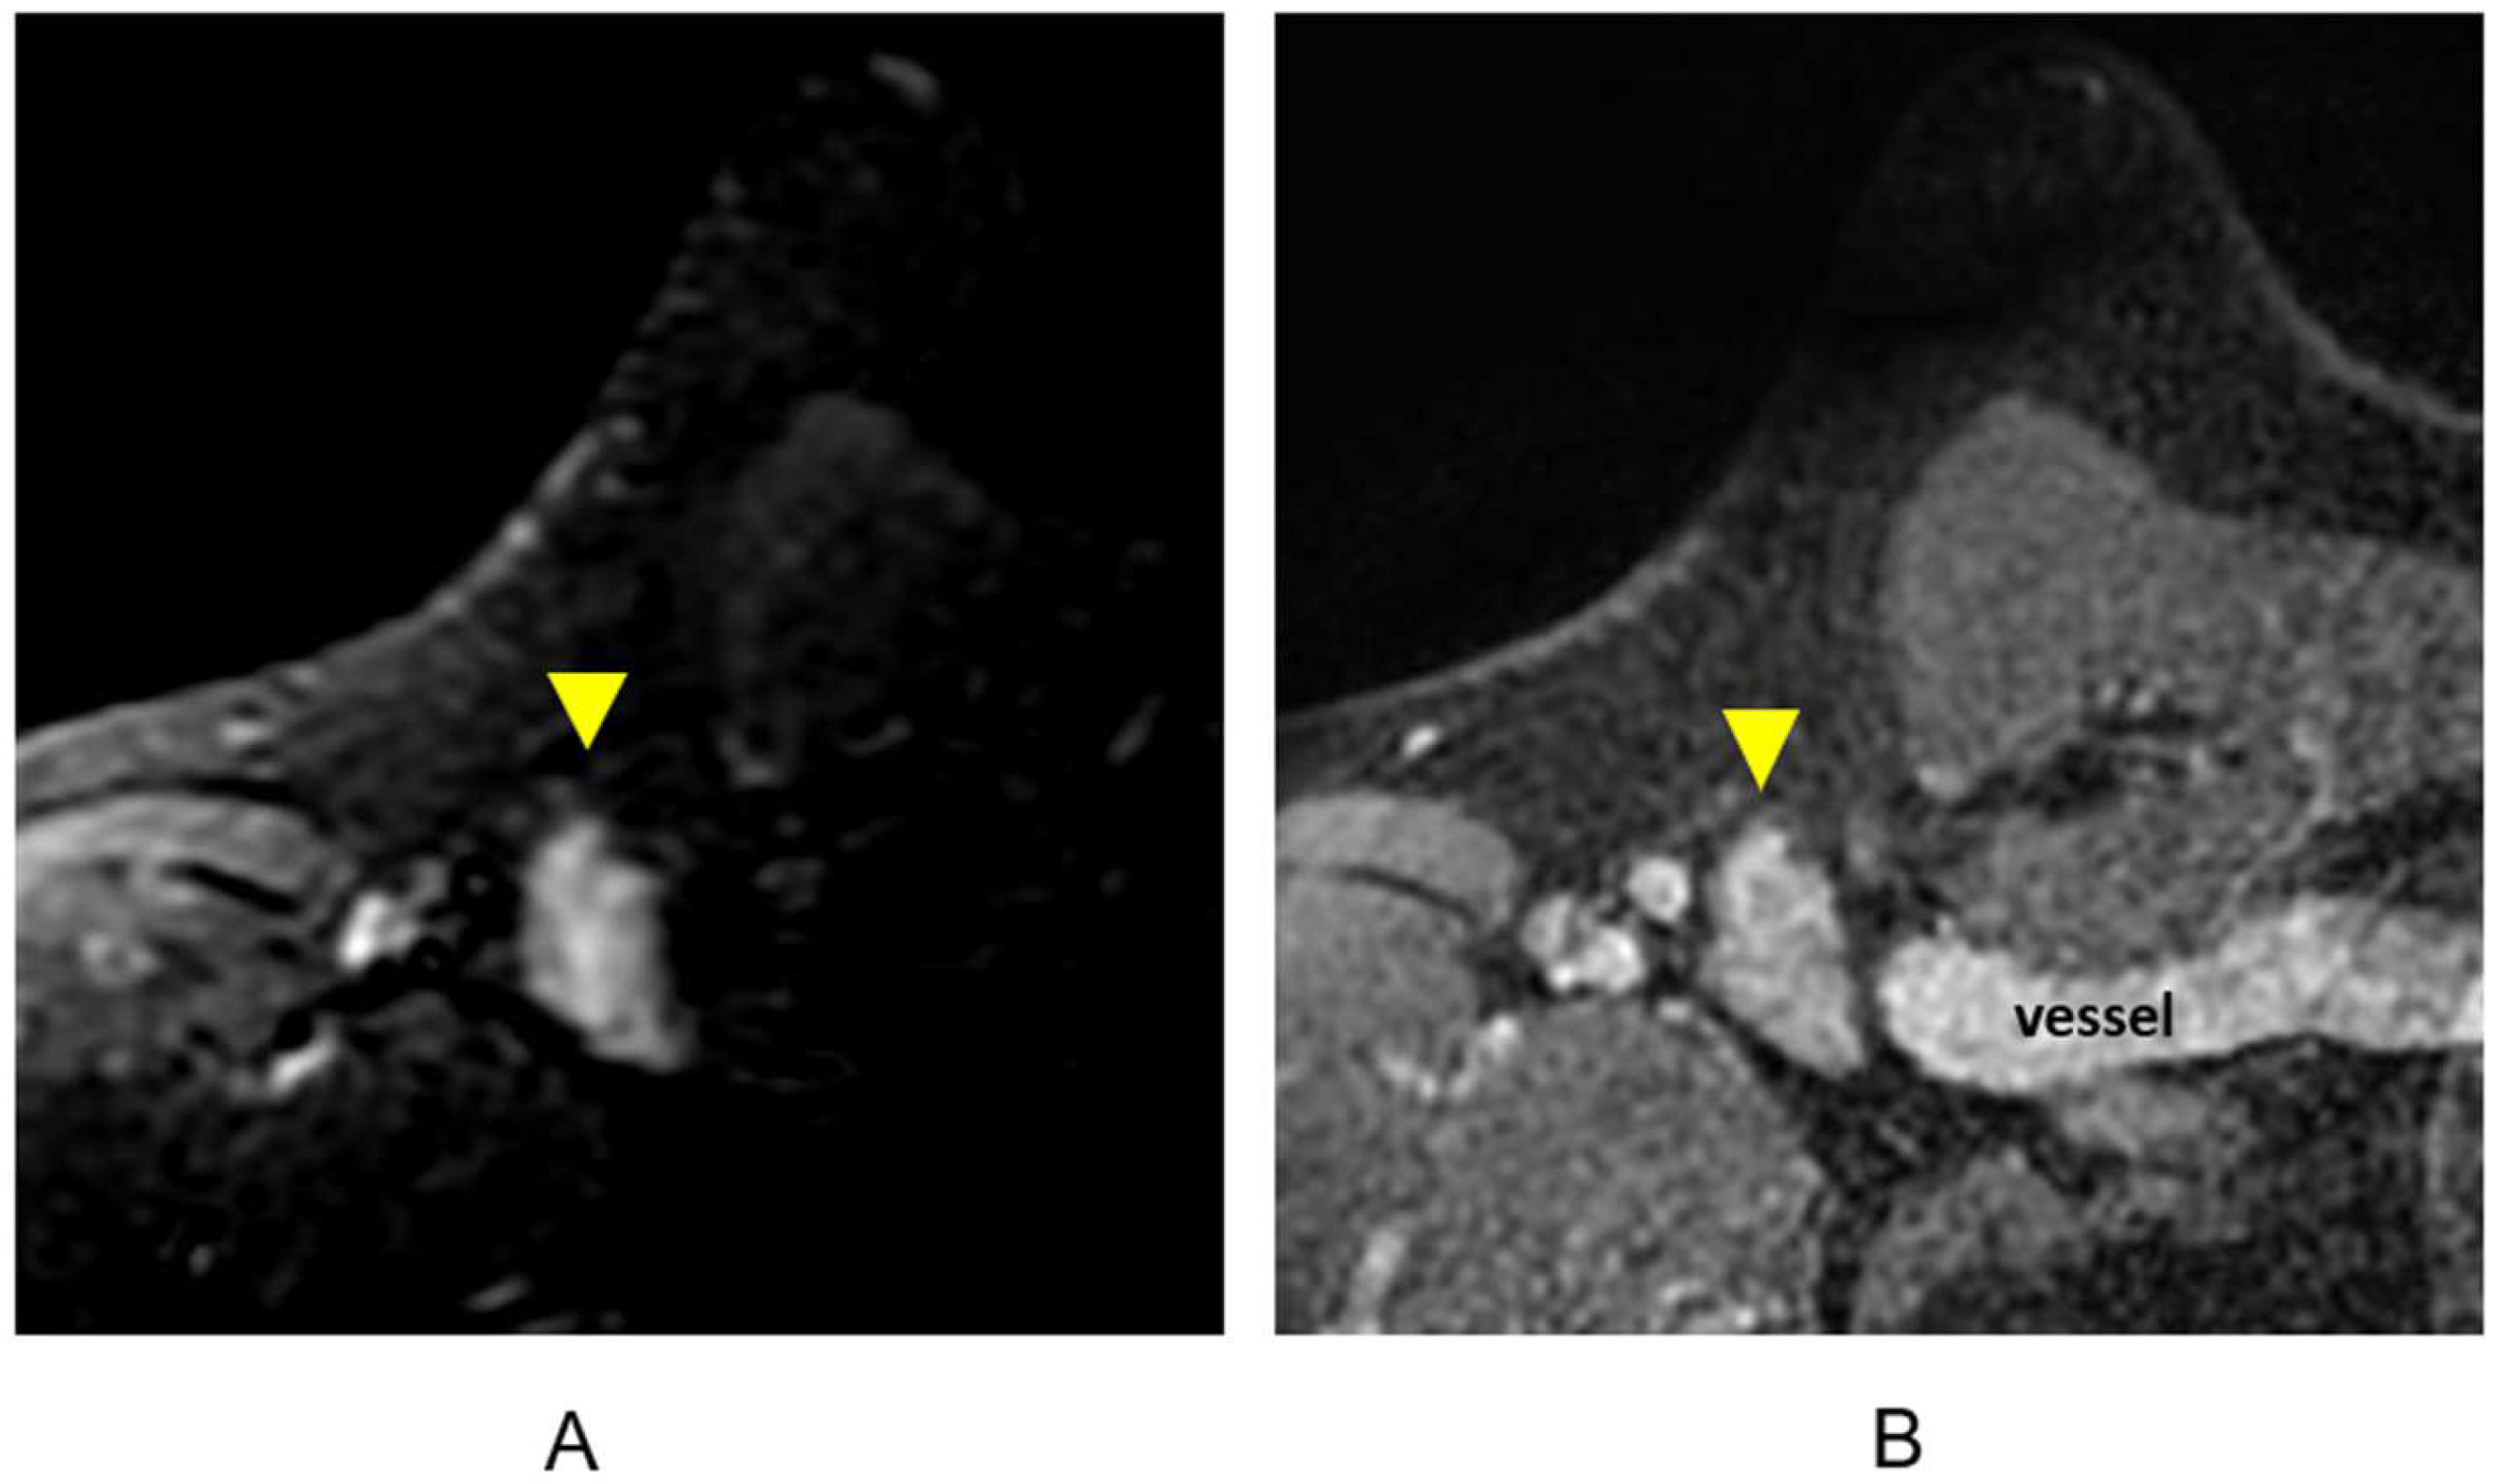

The cortex of a lymph node has decreased signal intensity on T1-weighted sequences and increased signal intensity on T2-weighted and STIR sequences [36]. Both benign and metastatic lymph nodes can enhance rapidly and homogeneously with washout kinetics at DCE MR imaging [51,52,53]. Although lymph nodes are hyperintense on a T2 or STIR sequence (Figure 10A), lymph node morphology and margins may be characterized on the post-contrast T1-weighted fat-suppressed sequences (Figure 10B). The post-contrast T1-weighted sequences will also depict muscles, vessels, and other anatomic landmarks.

Figure 10.

Lymph node (arrowheads). (A) Axial STIR sequence; (B) axial post-contrast T1-weighted fat-suppressed sequence.